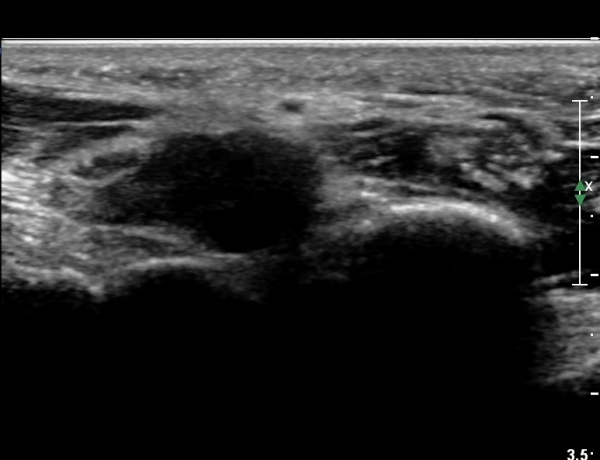

[½Å°æ] °áÀýÁ¾¿¡ ÀÇÇÑ ¼Õ¹Ù´Ú ºÎÀ§¿¡¼­ ô°ñ½Å°æ ½ÉºÎ °¡Áö º´Áõ(PN of deep branch of ulnar nerve at palm level due to ganglion)

4 sono.jpg

¼Õ¹Ù´Ú ºÎÀ§¿¡¼­ ô°ñ½Å°æ ½ÉºÎ °¡Áö º´Áõ

(periphral neuropathy  of  deep palmar branch of ulnar nerve at palm level).